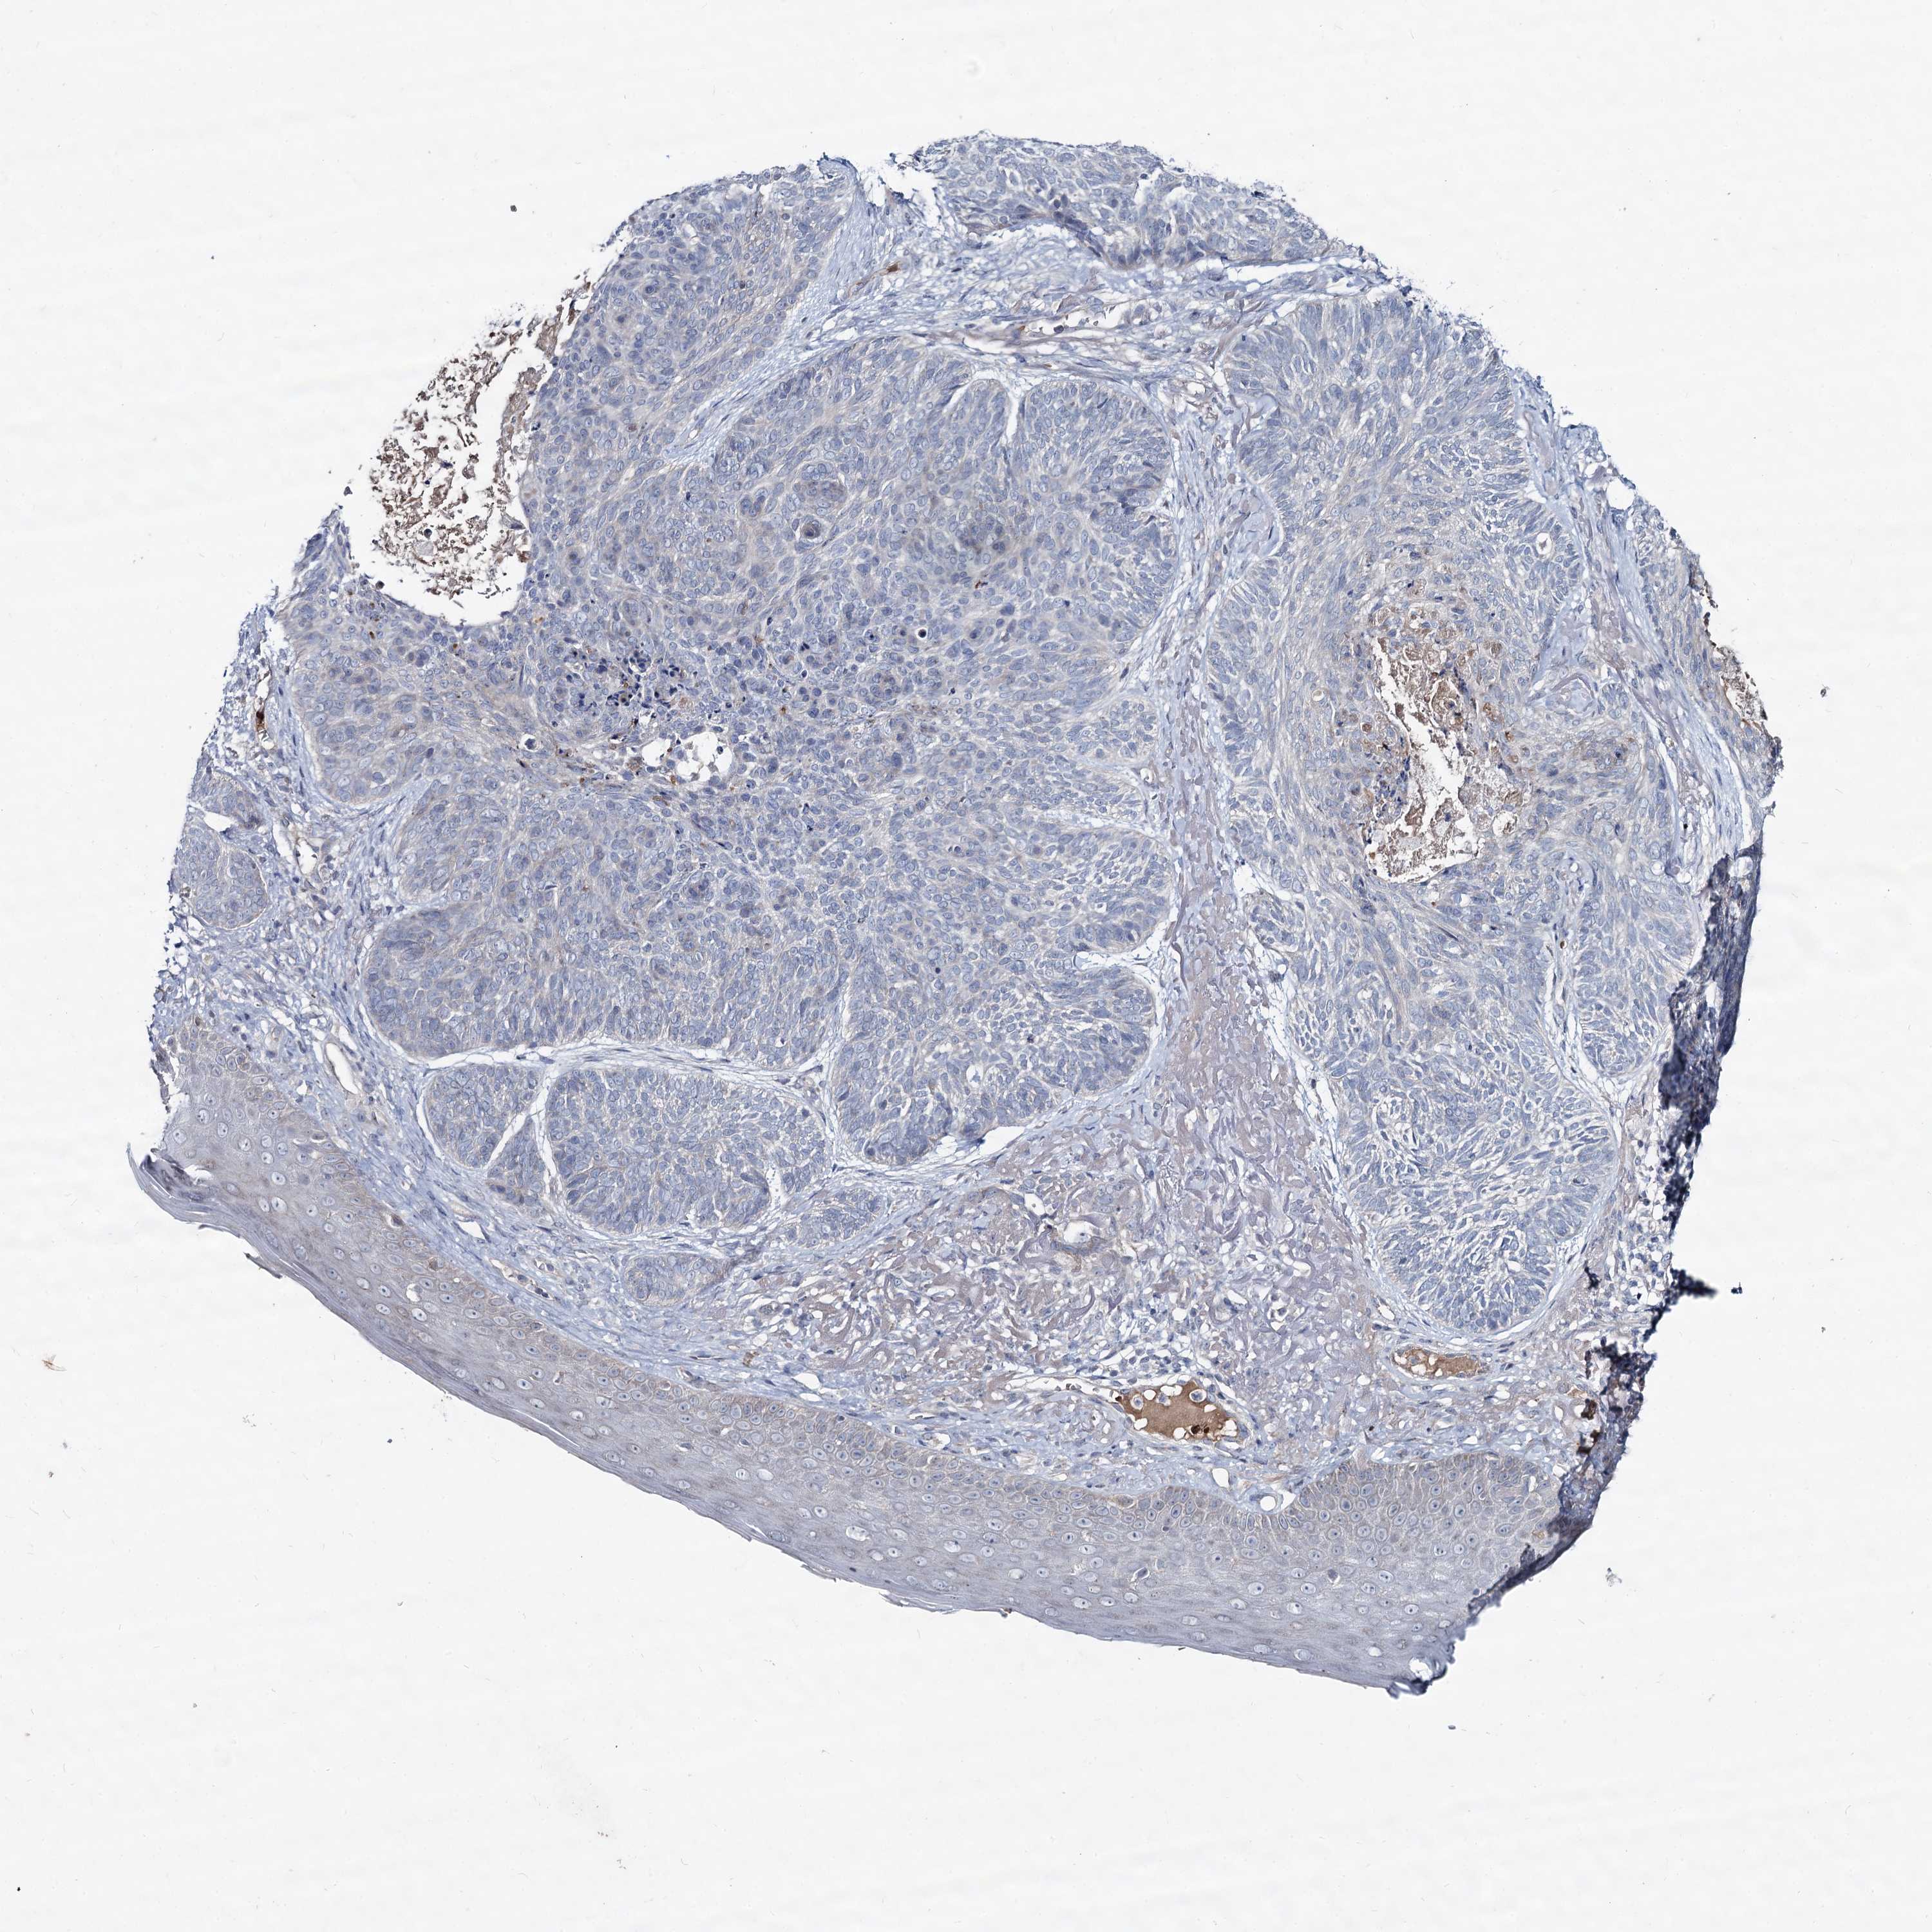

Basal cell and squamous cell cancer

SKIN CANCER - Protein expressioni

A mouse-over function shows sample information and annotation data. Click on an image to view it in a full screen mode. Samples can be filtered based on level of antibody staining by selecting one or several of the following categories: high, medium, low and not detected. The assay and annotation is described here.

Antibody stainingi

Antibody staining in the annotated cell types in the current human tissue is reported as not detected, low, medium, or high, based on conventional immunohistochemistry profiling in selected tissues. This score is based on the combination of the staining intensity and fraction of stained cells.

Each image is clickable and will lead to virtual microscopy that enables deeper exploration of all samples and also displays staining intensity scores, fraction scores and subcellular localization as well as patient and tissue information for each sample.

Antibody HPA039343

Antibody HPA040048

Staining

High

Medium

Low

Not detected

Basal cell carcinoma